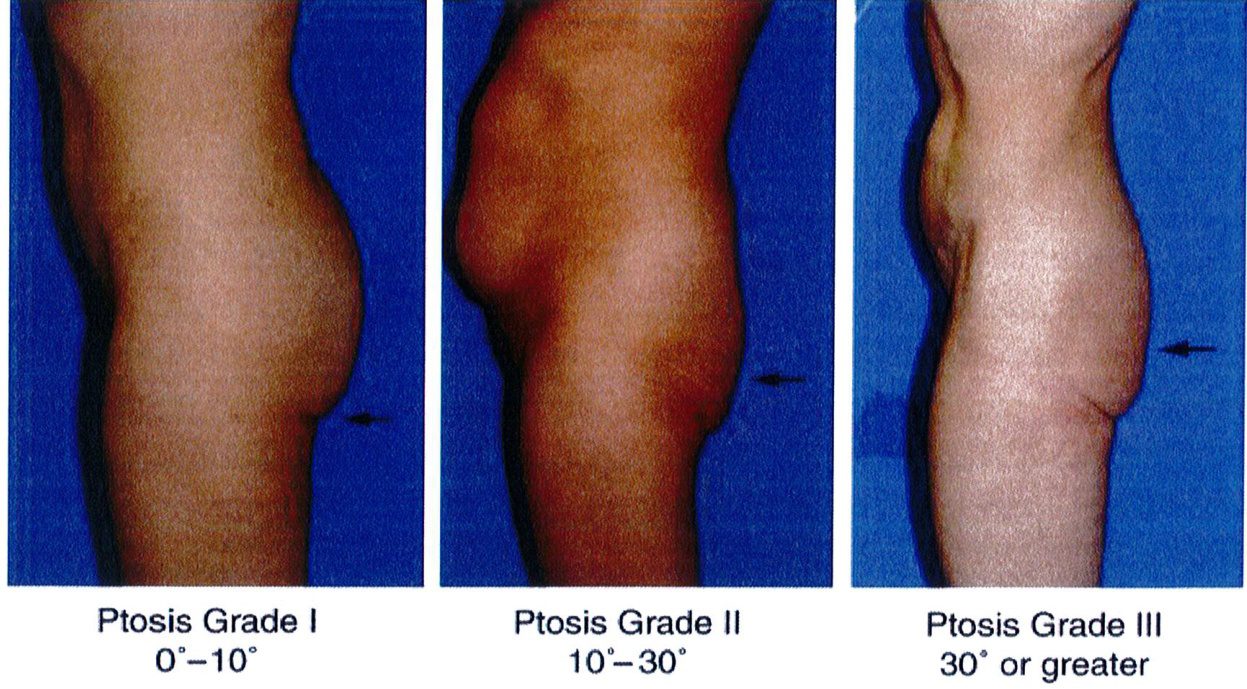

Bước cuối cùng khi đánh giá vùng mông là đánh giá tình trạng sa mông. Đế đánh giá, nên đứng ỏ phía bên để nhìn và phân loại sa mông (từ không sa đến có sa), cả 2 loại này đều được phân loại thành 3 phân lớp phía dưới chúng. Việc phân loại này quyết định xem nên thực hiện quy trình nào cho bệnh nhân.

Phân loại sa mông

Phân loại này được áp dụng khi có vùng da sa xuống dưới nếp lắn mông và chúng được chia thành 3 giai đoạn I, II, III (Hình 28).

Giai đoạn I

GĐ I rất giống với phân loại không sa – lớp C; tuy nhiên, một phần thể tích mông và da sa xuống dưới nếp lằn mông (mức độ ít). Khi nhìn nghiêng, sẽ phát hiện 1 nếp lằn rõ nằm ngang. Trong những trường hợp này, chỉ cần làm đầy mông mà không cần nâng mông trên.

Ở một nhóm rất nhỏ bệnh nhân có sa mông giai đoạn I, việc cắt bỏ vùng da thừa dưới nếp lằn mông có thể được xem xét nhưng việc thực hiện chúng cực kỳ hiếm khi xảy ra. Các tác giả khuyên nên thực hiện làm đây trước và sau đó đánh giá lại vùng mông sau khoảng 3-6 tháng.

(Hình 28). Ở đây cũng có thể xuất hiện tình trạng mất đàn hồi da và xuất hiện các vết rạn da. Nếu các vết rạn xuất hiện ở khu vực điểm B và C thì nên chỉ định nâng mông; tuy nhiên, đa số trường hợp giai đoạn II chỉ cần làm đầy mông là đủ. Những bệnh nhân này cũng có thể phải cắt bỏ phần da thừa ở gần nếp lẵn mông. Nhưng tác giả khu- yến nghị là nên thực hiện làm đầy mông trước và sau đó đợi từ 3 tới 6 tháng để xem liệu có cần cắt bỏ vùng da thừa đó hay không.

Giai đoạn II

Bệnh nhân ở giai đoạn II, nếp lằn mông vẫn còn nhìn thấy nhưng có tổ chức da sa xuống dưới nếp lắn. Trong khi nếp lắn mông ở giai đoạn I còn nằm ngang thì giai đoạn Il có góc cạnh hơn. Cụ thể, thường có một độ lõm nhất định ở phần trên của vùng mông dưới

Bệnh nhân ở giai đoạn này có phần da chùng nhiều nhất, xuống dưới nếp lằn mông khi nhìn từ phía

của từng đơn vị thẩm mỹ vùng mông sẽ giúp xác định những khu vực nào cần làm đầy/hút mỡ/cắt bỏ hoặc đặt đường rạch.

bên. Nếp lằn này mở rộng về phía mặt trong đùi, và góc tạo bởi chúng và đường liên mông thường lớn hơn 30°. Giai đoạn này cũng được mô tả bởi chỗ lõm ở phân dưới của khu vực trung tâm (hình 28). Các vết rạn da xuất hiện chủ yếu ở vùng điểm B, và da có độ đàn hồi kém với các vết rạn rải rác. Điều trị bệnh nhân ở giai đoạn này cần thực hiện nâng mông trên, cắt vùng da thừa dưới nếp lằn mông và làm đầy mông. Trong các thủ thuật này, có thể thực hiện 1 trong 3 trước đều được.

Ptosis Grade I 0°-10°: Sa mông GĐ 1 0°-10° Ptosis Grade II 10º-30º Ptosis Grade III 30° or greater: Sa mông GĐ III 30° hoặc hơn

Ptosis Grade II 10°- 30°

Hình. 28. Giai đoạn I, II, III của bệnh nhân có tình trạng sa mông. Ở giai đoạn I, góc tạo bởi nếp da nhỏ hơn 10 độ. Ở giai đoạn II, focs này rơi vào khoảng từ 10- 30 độ. Còn ở giai đoan III, góc tao bởi nếp da lớn hơn 30 đô.